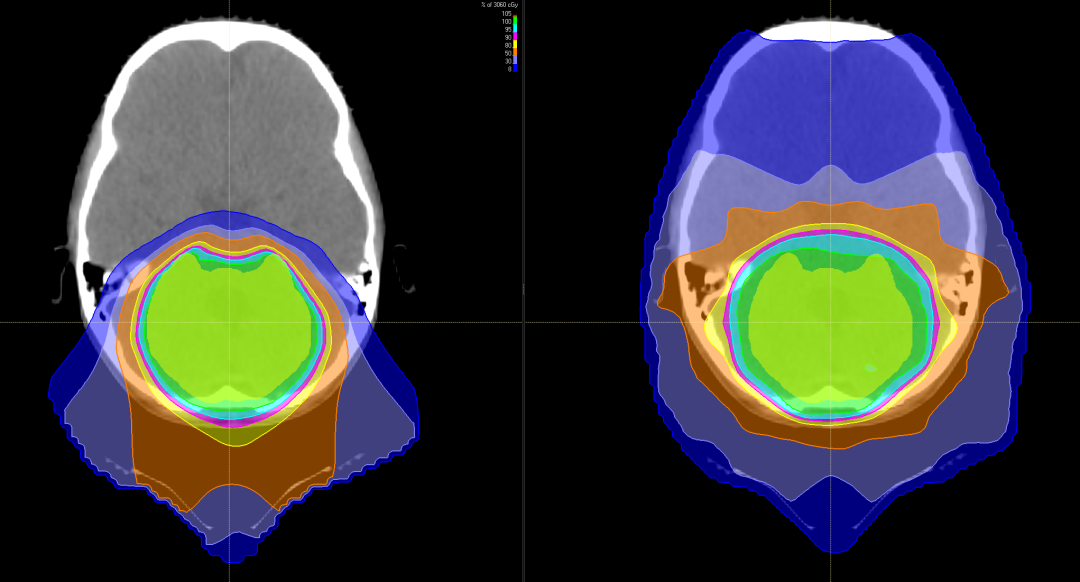

与X线调强放疗(IMXT)相比,笔形束扫描(PBS)质子治疗具有更优的剂量适形性及靶区覆盖情况。

有研究表明,儿童神经母细胞瘤使用质子治疗的最大效益在于减少脑部正常组织构造的损伤,进而降低长期伤害。质子治疗是一种比其他任何形式的放射治疗更准确,更精确地靶向肿瘤,同时保留健康组织,目前全球最先进的一种放疗技术。通过质子治疗,可以最大限度地避免靶标外部的绝大多数不必要的辐射。

与传统形式的辐射相比,质子束会到达肿瘤内部的精准位置而不是沿着光束离开人体的路径释放大部分辐射剂量。实际上,质子没有肿瘤之外的辐射“退出剂量”,这意味着质子停在肿瘤上,不会继续伤害身体的健康部位。